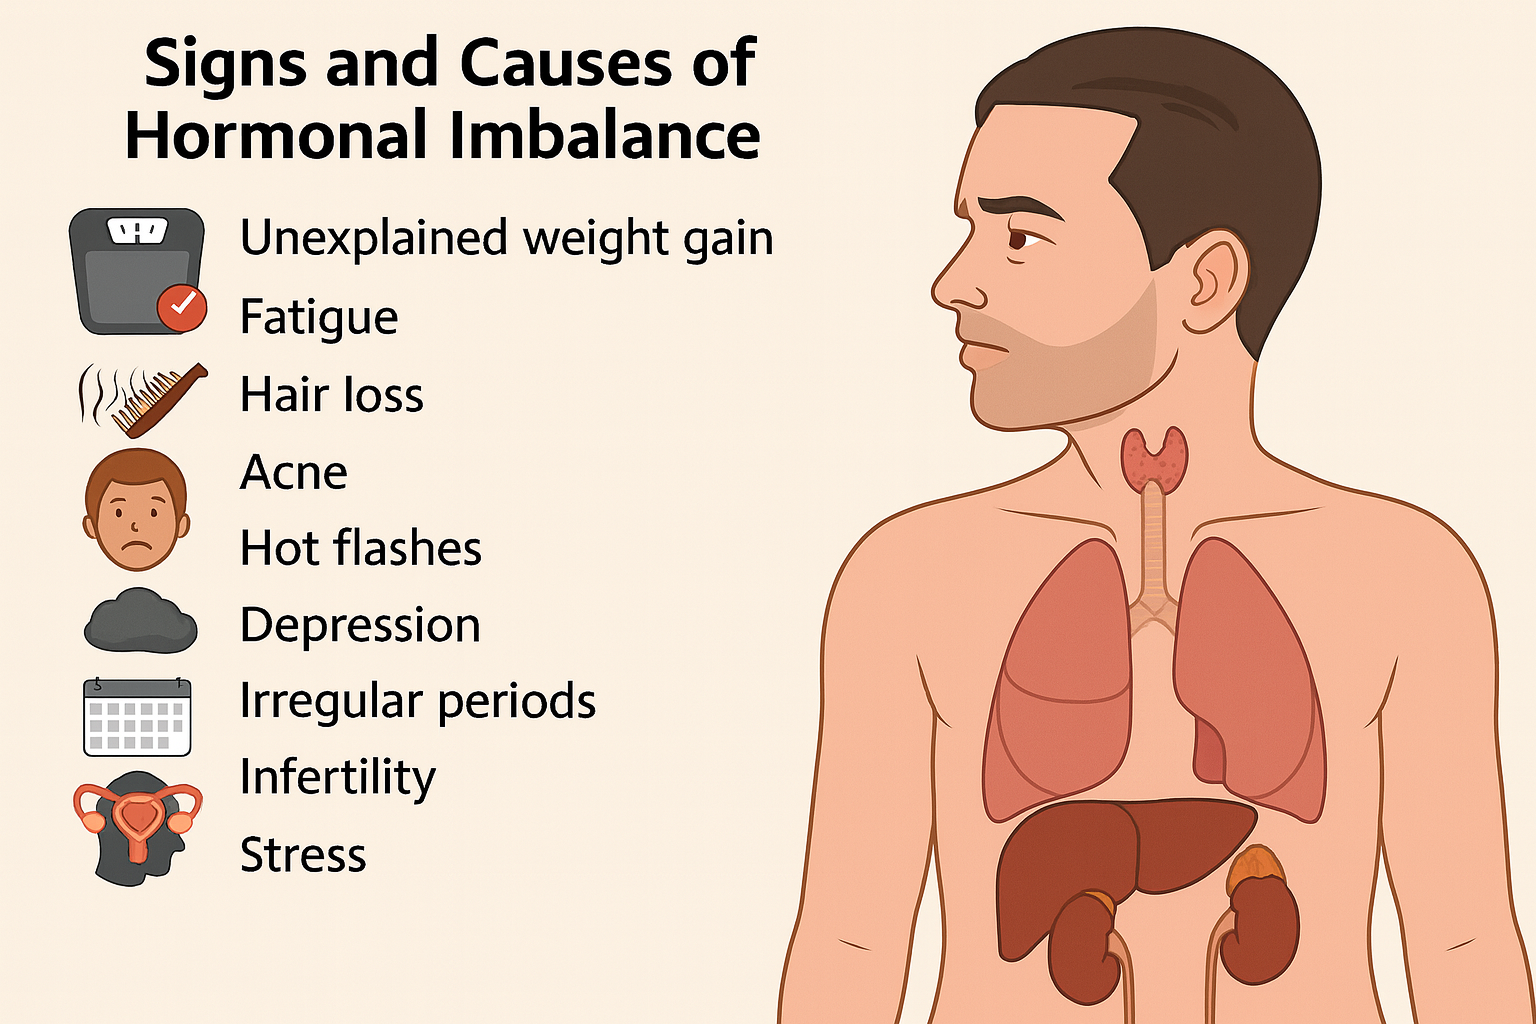

علائم و علل عدم تعادل هورمونی

عدم تعادل هورمونی میتواند باعث بروز علائمی مانند خستگی، تغییرات خلقی، اختلالات خواب، افزایش یا کاهش وزن و مشکلات پوستی شود. آشنایی با علل و نشانههای این وضعیت، نقش مهمی در پیشگیری و درمان بهموقع آن دارد.

نشانههای عدم تعادل هورمونی چیست؟

از آنجا که بدن انسان بیش از ۵۰ نوع هورمون تولید میکند و هرکدام در فرآیندهای حیاتی نقش دارند، طبیعی است که علائم این اختلال میتواند بسیار متنوع باشد. بسته به اینکه کدام هورمون دچار نوسان شده است، نشانهها نیز متفاوت خواهند بود.

نکته مهم این است که بسیاری از این علائم میتواند ناشی از بیماریهای دیگر هم باشد، نه فقط عدم تعادل هورمونی. بنابراین اگر تغییر تازهای در وضعیت سلامتی روزمرهتان مشاهده کردید، چه علائم خفیف و چه شدید، باید آن را جدی بگیرید و با پزشک مشورت کنید. تشخیص بهموقع میتواند تفاوت بزرگی در روند درمان ایجاد کند.

علائم میتوانند بسته به نوع هورمون متفاوت باشند، اما مواردی مانند خستگی مداوم، تغییرات ناگهانی وزن، اضطراب، مشکلات خواب، ریزش مو، بینظمی قاعدگی، کاهش میل جنسی و تغییرات خلقی از شایعترین نشانهها هستند.